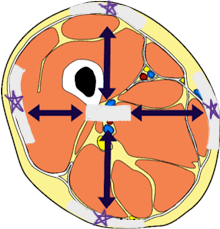

sagittal plane

frontal/coronal plane

transverse plane

dorsal/posterior

ventral/anterior

lateral

medial

distal

proximal

superficial

deep

cranial cavity

vertebral cavity

pleural cavity

pericardial cavity

mediastinum

abdominal cavity

pelvic cavity